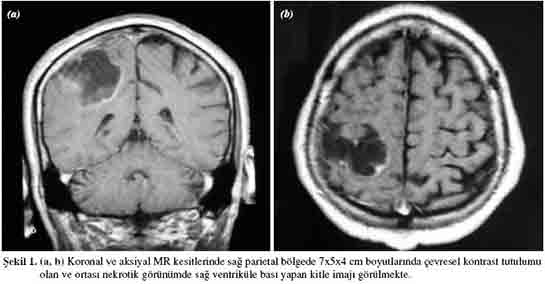

Beyin metastazının tanısı, genellikle görüntüleme yöntemleri ile konulmaktadır. Bu yöntemler arasında:

• Manyetik rezonans görüntüleme (MRG)

Bu görüntüleme yöntemleri, beyin dokusundaki anormalliklerin belirlenmesi ve metastatik lezyonların sayısının ve boyutunun değerlendirilmesi açısından büyük önem taşımaktadır.